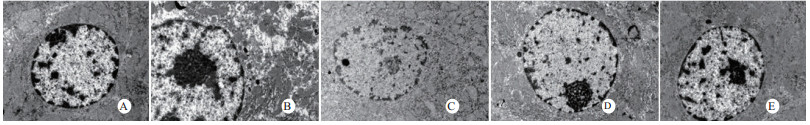

光镜下可见,假手术组肺泡大小形态均匀,结构清晰,肺泡腔内无出血和白细胞浸润;感染性休克组肺泡壁破坏严重,血管壁和肺泡间隔明显增厚;U50488H+感染性休克组大部分肺泡腔均匀一致,肺间隔略增厚,肺泡壁轻度水肿,但出血和白细胞浸润情况比感染性休克组明显减轻(图 1)。假手术组心肌细胞大小一致,排列整齐,核浆比正常,心肌细胞核呈椭圆型,胞浆均匀红染;感染性休克组心肌细胞肿胀,体积明显增大,细胞核大而异型,核内染色质固缩、边集,白细胞浸润明显增加;U50488H+感染性休克组多数心肌细胞形态相对正常,少数心肌细胞呈现脂肪变性(图 2)。假手术组肝细胞结构完整,肝小叶形态正常;感染性休克组肝细胞显著肿胀、呈空泡样和点状/小片状坏死;U50488H+感染性休克组肝细胞轻度肿胀,未见明显坏死灶、肝血窦扩张和炎性细胞浸润(图 3)。假手术组肾组织结构大致正常;感染性休克组肾小管细胞轻度水肿、空泡变性;U50488H+感染性休克组肾小管形态大致正常,间质无明显出血水肿(图 4)。

| A:假手术组,B:感染性休克组,C:U50488H+感染性休克组,D:nor-BNI+U50488H+感染性休克组,E:nor-BNI+感染性休克组 图 1 各组光镜下肺组织病理学改变(HE×400) Fig 1 Histopathological features of lung(HE×400) |

本研究还进一步观察了感染性休克大鼠重要脏器的病理学变化与超微结构。结果发现,感染性休克时,肺泡壁破坏严重,血管壁和肺泡间隔明显增厚,炎症细胞浸润较多,肺泡明显压缩畸形,肺泡隔肿胀,扭曲,隆起。该结果与潘景业等的报道一致。同时实验发现,U50488H可减轻感染性休克肺泡壁出血水肿与肺组织炎性细胞浸润,抑制肺间隔增厚。实验还观察到感染性休克大鼠心肌纤维肿胀、扭曲、断裂、溶解,并由此导致心功能障碍。U50488H亦可减轻线粒体肿胀崩解和心肌细胞溶解与坏死,可能与U50488H减轻心肌抑制有关[12],具体机制与分子通路尚需进一步实验验证。本研究还观察到感染性休克大鼠肝细胞出现肿胀、空泡样脂肪变性和点状/小片状坏死,毛细胆管明显增多、扩张;肾小管细胞轻度水肿、空泡变性,肾小管上皮细胞微绒毛缺失,细胞崩解,肾小管上皮断裂。预先给予U50488H可显著减轻感染性休克肝细胞浊肿、肝血窦扩张和炎性细胞浸润;抑制肾小管上皮细胞核变形、微绒毛坏死和间质出血水肿。nor-BNI可阻断这一效应。上述结果均提示U50488H可通过激动κ-阿片受体,改善肝脏和肾脏血流量保护感染性休克肝脏和肾脏功能,具体机制可能和细胞凋亡等相关。